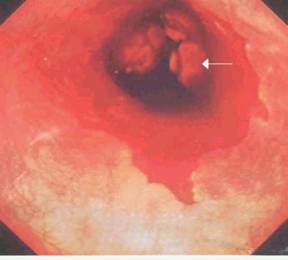

4.食管內鏡檢查此為最適宜的明確食管炎的方法,結合病理學檢查,能反映食管炎的嚴重程度,其敏感性為95%,特異性為41%。但此法不能反映反流嚴重程度,僅反映食管炎嚴重程度,對判斷輕度(Ⅰ級)食管炎困難,故大部分學者提出,內鏡顯示Ⅰ或Ⅱ級食管炎不需作黏膜活檢,只在鏡檢不明顯或有可疑變化時作Rubin管吸引活檢,但原則上新生兒期不做。黏膜活檢也是診斷Barrett食管的主要依據。內鏡下反流性食管炎的分型:

(1)Savary-Miller分型(1978):Ⅰ:孤立糜爛灶與紅斑灶和(或)滲出;Ⅱ:散在糜爛和潰瘍,未波及食管全周;Ⅲ:糜爛和潰瘍波及食管全周,但未形成狹窄;Ⅳ:慢性病損或潰瘍,同時有食管壁的纖維化、狹窄、短食管和(或)柱狀上皮食管。

(2)Jamieson分型:0:正常黏膜;Ⅰ:孤立發紅區;Ⅱ:潰瘍形成;Ⅲ:食管狹窄形成。

(3)第九屆世界胃腸病會議分型:Ⅰ:稀疏、垂直的糜爛或潰瘍;Ⅱ:融合性潰瘍;Ⅲ:潰瘍融合成環狀;Ⅳ:瘢痕、狹窄。